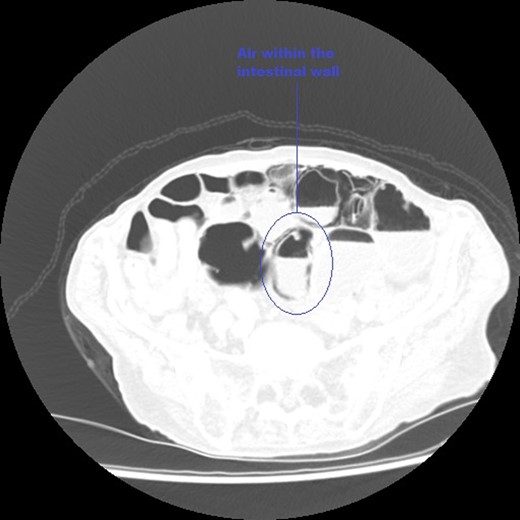

An axial CT image of the pelvis in lung view windows, taken at initial presentation clearly demonstrating intra-mural air within the bowel, marked on image.